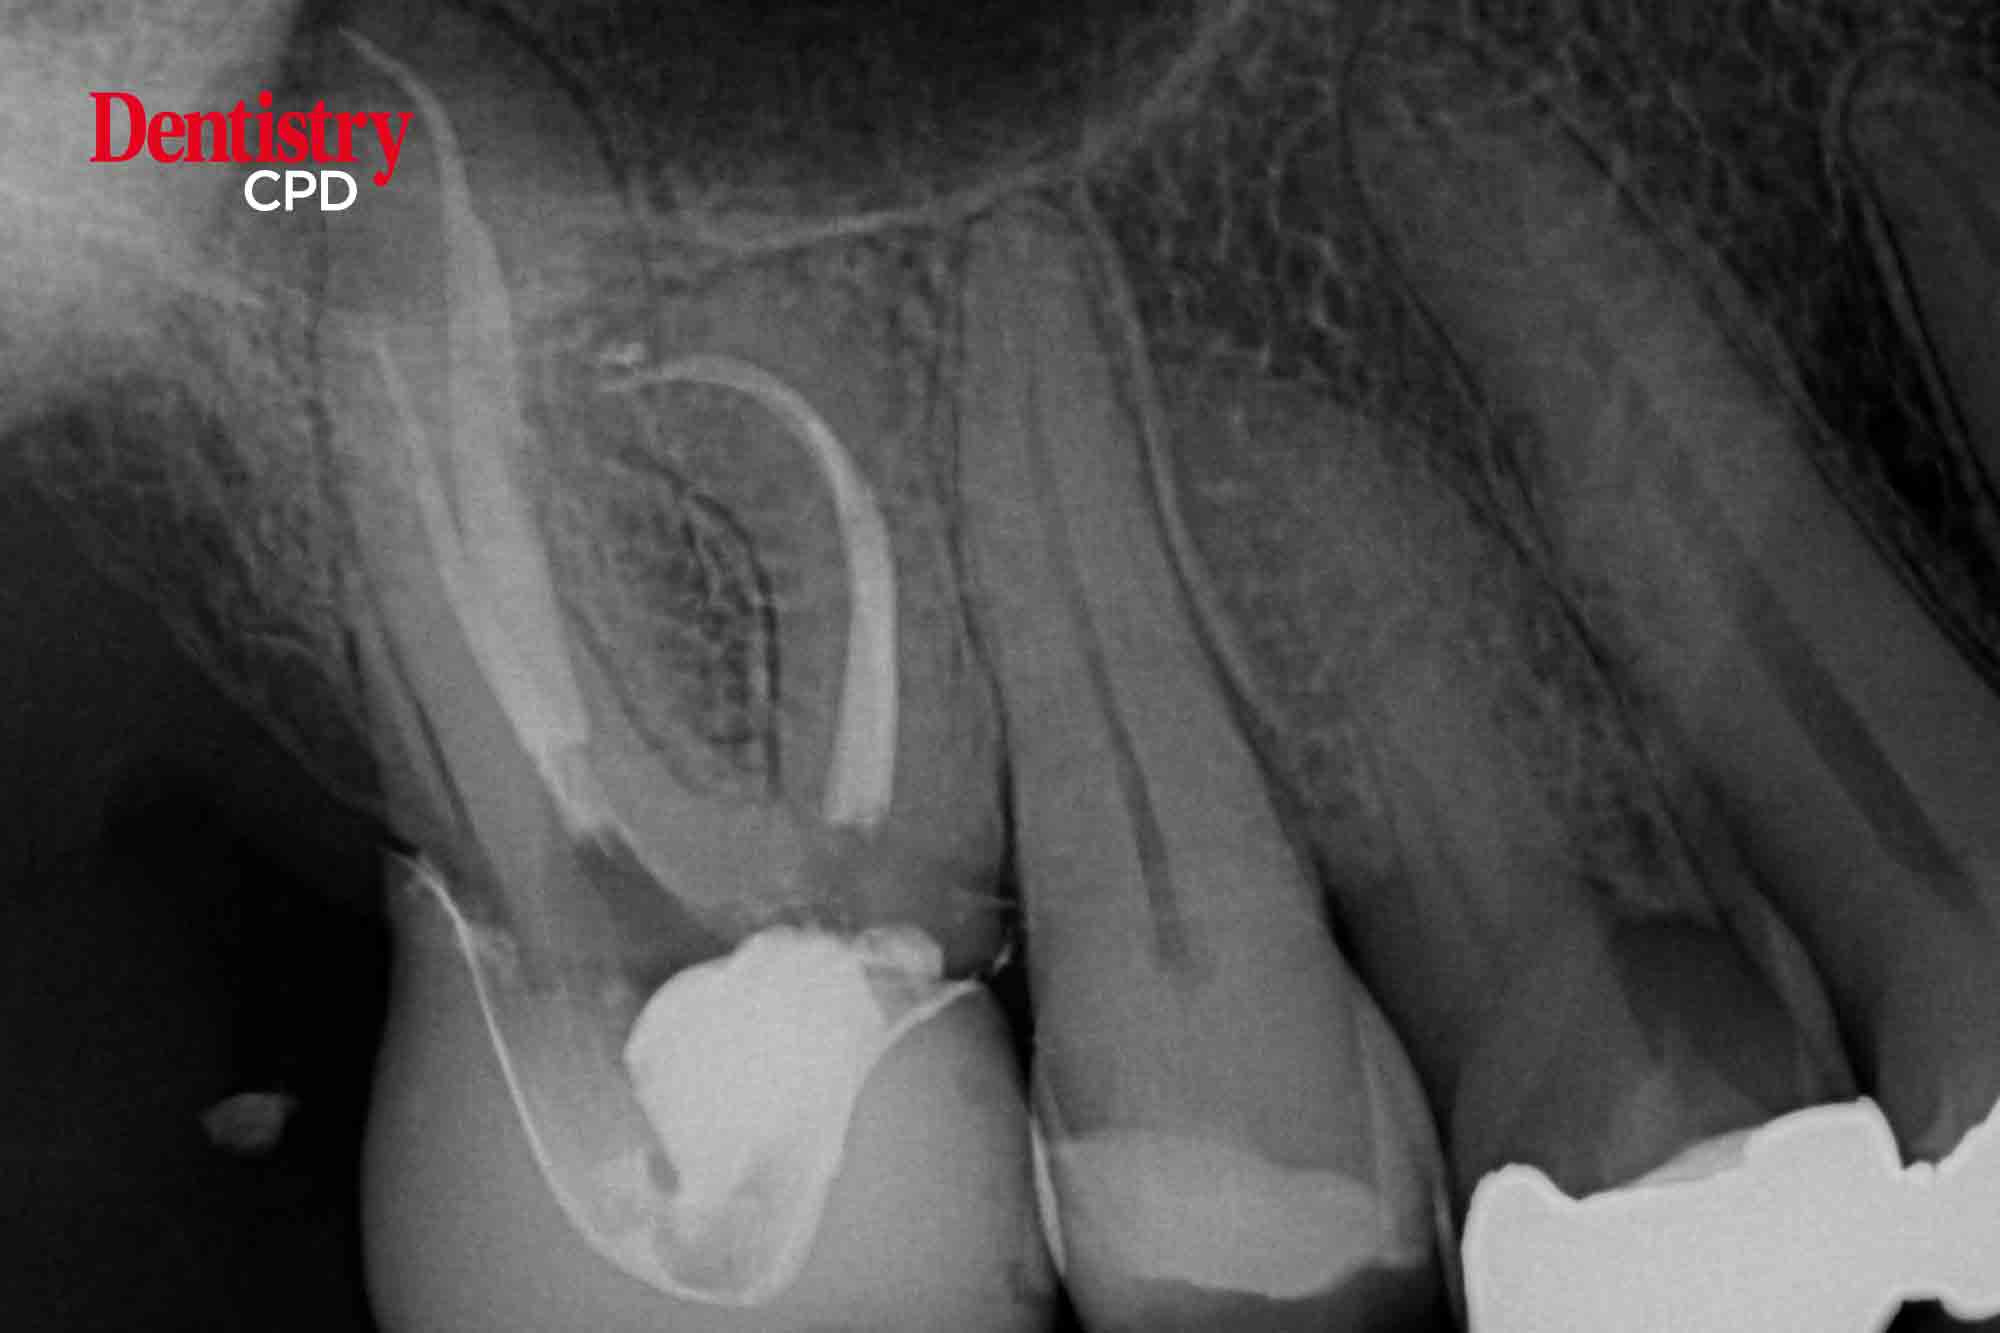

Where are we with endodontic radiography?

Tony Druttman provides an update to the current status of radiography within endodontics.

To provide an update on endodontic radiography.